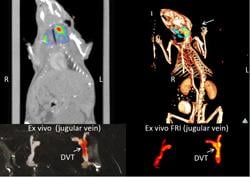

June 7, 2011 — Research presented at the Society of Nuclear Medicine's annual meeting showed a novel optical imaging technique called near-infrared fluorescence (NIRF), which can image dangerous blood clots hiding inside elusive veins. The imaging technique uses light energy with a newly synthesized imaging agent to glean information about cells and tissues. The agent uses a biomarker that seeks out fibrin peptide that is actively involved in the formation of clots.

In conjunction with the new near-infrared fluorescence fibrin-targeted peptide, investigators were able to successfully detect fibrin-rich deep vein thrombosis with both intravital fluorescence microscopy and noninvasive fluorescence molecular tomography, which allows researchers to acquire information about tissues by analyzing how light is absorbed by and scattered from tissues. By coupling the fibrin peptide agent (EP-2104R) with rapidly emerging intravascular NIRF imaging, researchers now have the opportunity to study micro-thrombi on coronary artery plaques and coronary stents that are at especially high risk for thrombosis and vessel occlusion, the main cause of heart attacks. This could help clinicians predict potential heart attacks and other major cardiovascular events before it is too late, thus potentially saving the lives of patients.